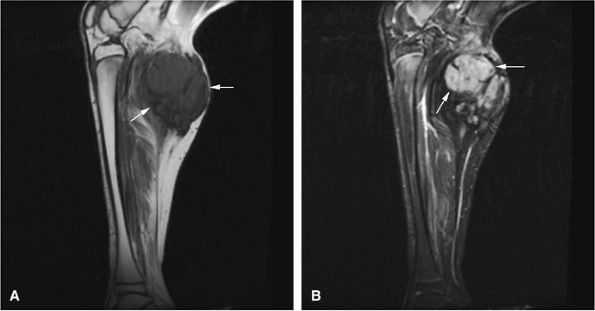

FIGURE 14-68 ● Telangiectatic osteosarcoma. (A) Coronal T1-weighted and (B) axial T2-weighted images show intraosseous and extraosseous tumor extension (white arrows) with heterogeneous cystic hemorrhagic components (white arrowhead) and fluid–fluid levels (black arrows).

Telangiectatic osteosarcomas are especially difficult to assess histologically because the viable cells and anaplastic cells are obscured by hemorrhage and necrosis or camouflaged within benign reactive cells of the walls, which simulates an aneurysmal bone cyst (Fig. 14-67).72,74 It was thought to have a worse prognosis than conventional osteosarcoma, but now the prognosis is considered similar. On radiographs, the telangiectatic variant appears lytic because of the lack of demonstrable bone production. MR images show an aggressive, destructive lesion, usually accompanied by an associated soft-tissue mass. The inhomogeneity of signal intensity, with both low- and high-signal-intensity areas on T1- and T2-weighted images and fluid–fluid levels, reflects the high degree of vascularity and the presence of large hemorrhagic cystic spaces (Fig. 14-68).